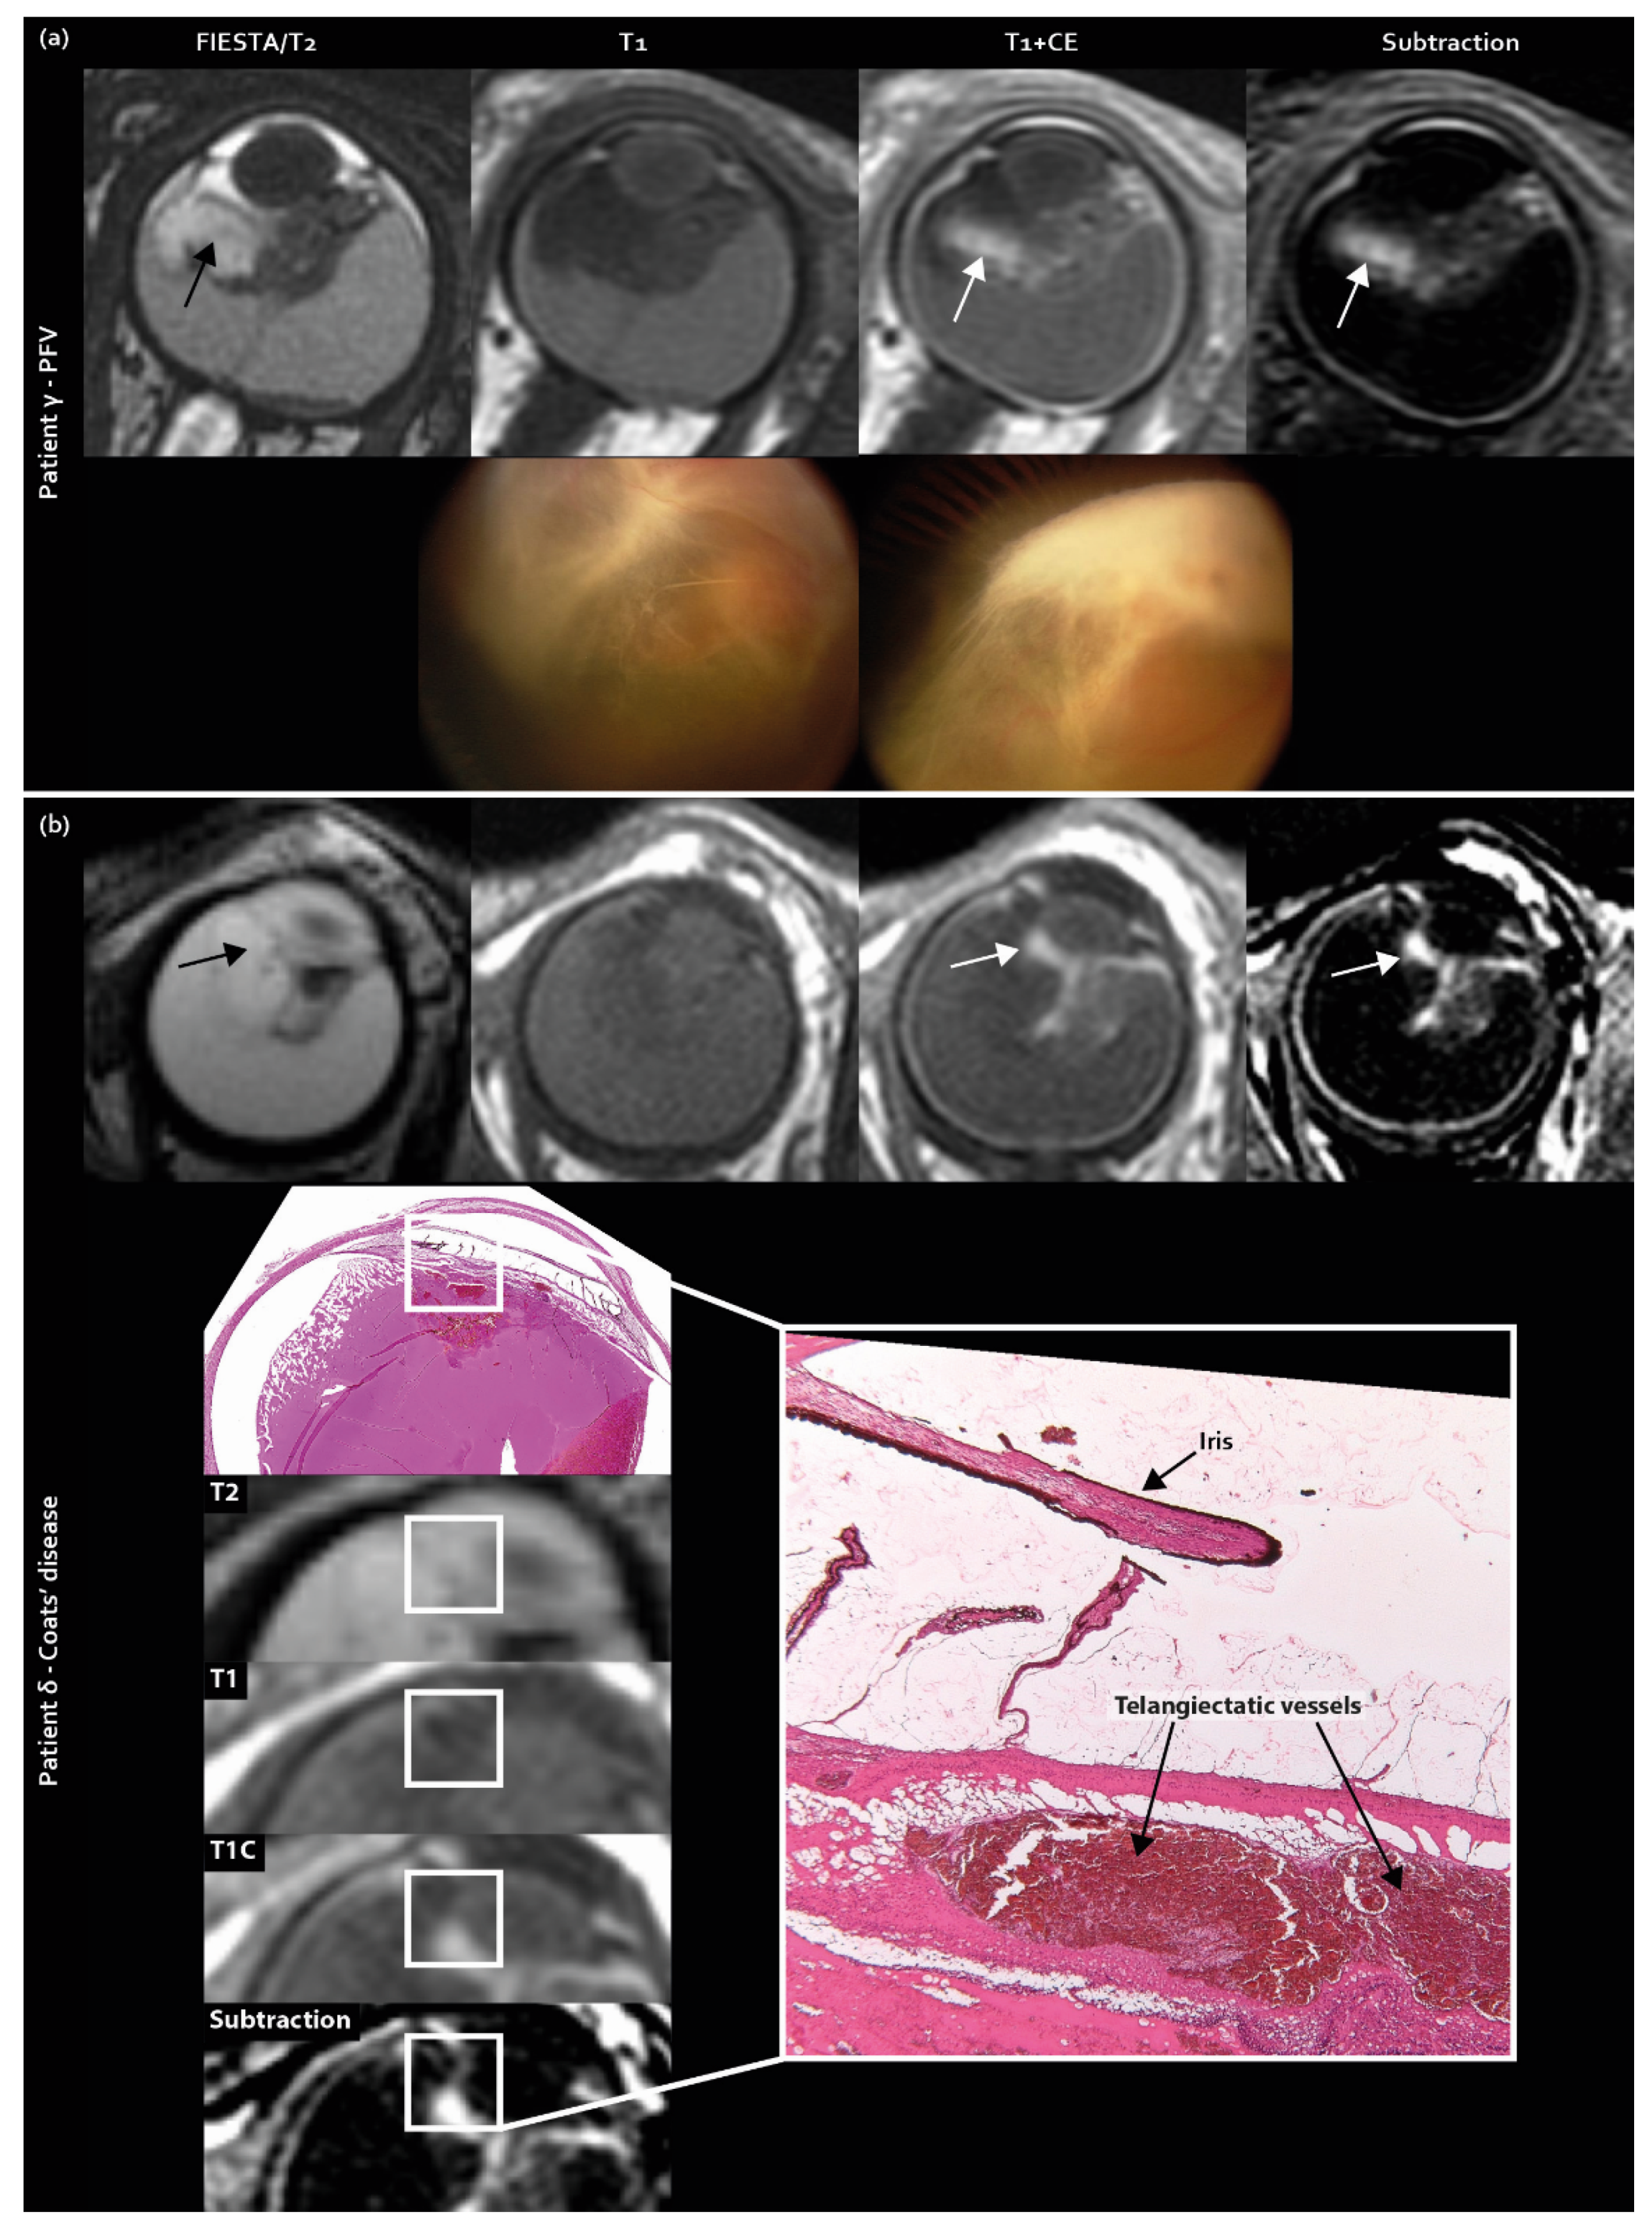

Contrast enhancement outside the solid mass lesion (T2-hypointense) was also included in the scoring list as a new imaging feature and was exclusively found in pseudoretinoblastoma (Coats’ disease 30% [7/23], PFV 57% [4/7] retinoblastoma 0% [0/34], p < 0.001 (Figure 2)).

Figure 2.

Contrast enhancement outside the solid lesion (enhancement mismatch) as a newly identified MR imaging feature exclusively found in pseudoretinoblastoma (Coats’ disease and PFV/retinal dysplasia): (a) MR imaging of enhancement mismatch and corresponding Retcam fundus camera images showing elongated ciliary body processes in PFV patient γ; (b) MR imaging of enhancement mismatch with corresponding histopathology in Coats’ disease patient δ.

Secondly, contrast enhancement outside the solid area of the lesion (enhancement mismatch) was exclusively found in pseudoretinoblastoma, which can be explained by the increased leakage of contrast material from abnormal retinal vessels. In retinoblastoma, contrast enhancement is restricted to the retinal tumors, whereas the unaffected retina does not enhance. However, in pseudoretinoblastoma, vascular abnormalities are present throughout the retina (i.e., retinal telangiectasia in Coats’ disease) with a more wide-spread pattern of contrast leakage not necessarily confined to the retinal mass lesion [28]. The inter-rater agreement was poor for this MR imaging feature (enhancement outside the solid lesion), but post-hoc analysis showed that of the times any individual reader scored the presence of this feature, 42 out of the 44 times (96%) it involved a pseudoretinoblastoma diagnosis. The feature is not often detected in consensus by all readers, possibly due to its novelty (and hence showing a low agreement), but it is hardly ever encountered in retinoblastoma. This feature may show better agreement and discrimination performance when readers gain experience assessing it.